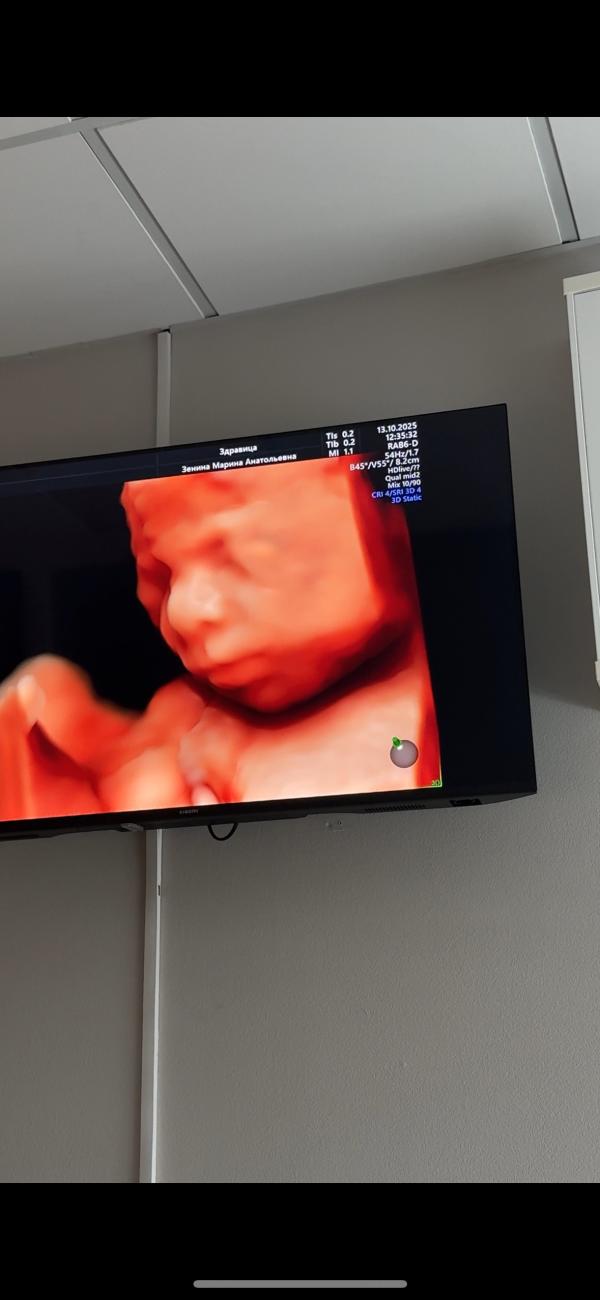

Была на узи , все хорошо с ним 🙏доча активная внизу поэтому и хорошо чувствуется. Это пацан на фотках)показал все прелести на экран,доча скрыла лицо не стала показывать себя 🙈